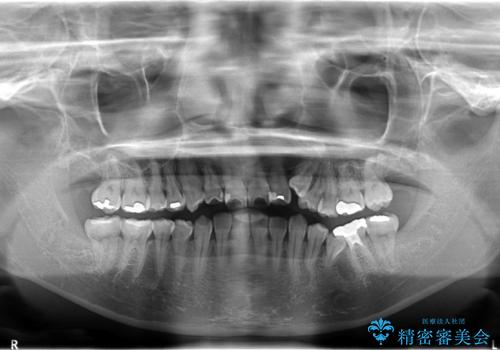

- 小臼歯4本抜歯によるハーフリンガル・ワイヤー矯正を計画した。

シビアな八重歯がきれいに歯列にはいることにより、笑った時の印象などもかなり大きく変わります。